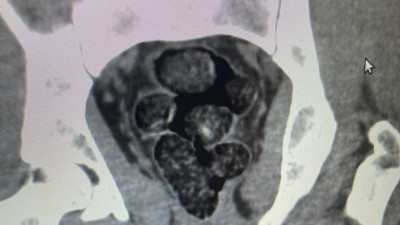

Midelerinden zehir çıktı Bingöl’de akıllara durgunluk veren bir olay gerçekleşti. Otobüs yolculuğu sırasında polis ekiplerince durdurulan yabancı uyruklu iki şahsın midesinden 10 parça halinde 113 gram metamfetamin çıktı.

Mide ve bağırsaklarından 51 kapsül uyuşturucu çıktı Samsun’da yakalanan zanlının mide ve bağırsaklarından 51 kapsül uyuşturucu çıktı.

Midesinde uyuşturucu taşıyan İranlı, havalimanında yakalandı İran'dan Samsun'a gelen İran uyruklu Matin M.'nin midesinde poşete sarılmış, 10 adet olmak üzere toplamda 191,18 gram metamfetamin ele geçirildi.

Yabancı uyruklu şahsın midesinden tam 53 paket çıktı. Nasıl girdiler ülkeye? Gümüşhane’de yolcu otobüsünde yol kontrolünde şüpheli hareketlerde bulunan bir yabancı uyruklu şahsın midesinden tam 53 paket (513,08 gram) metamfetamin çıktı.